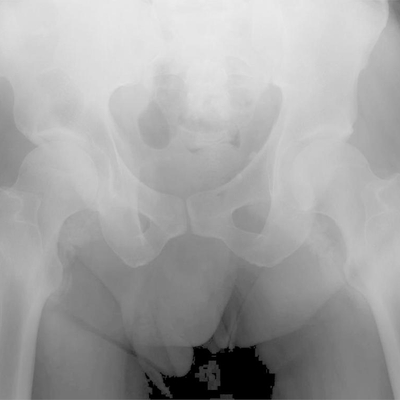

Click on an image below to view more info.